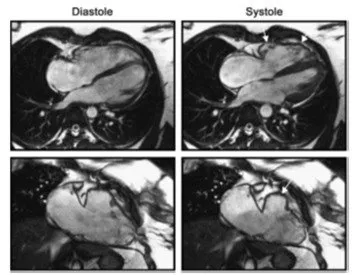

Chụp cộng hưởng từ tim đang trở thành công cụ đắc lực trong việc chẩn đoán suy tim nhờ nhiều ưu điểm vượt trội:

- **Độ chính xác cao**: Cung cấp hình ảnh 3D chi tiết về cấu trúc, chức năng và mô cơ tim.

- **Xác định căn nguyên của suy tim**: Dựa vào hình ảnh mô tả rõ ràng, các bác sĩ có thể phân biệt giữa suy tim do nhồi máu cơ tim và suy tim do các nguyên nhân khác.

- **Khả năng theo dõi diễn tiến bệnh**: CMR có khả năng quan sát và ghi nhận những thay đổi nhỏ nhất trong cấu trúc và chức năng tim theo thời gian.